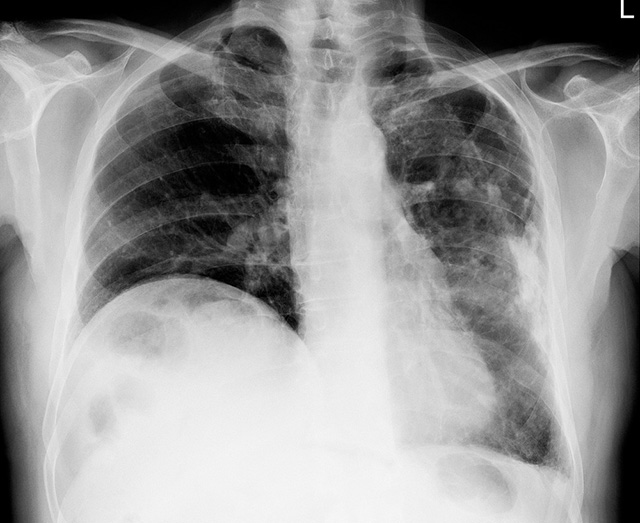

결핵 환자들이 코로나 감염 우려로 병원 방문을 줄이고, 임의로 약물 복용을 중단할 경우 다제내성결핵으로 이어질 위험이 커진다./클립아트코리아 제공

결핵 환자들이 코로나 감염 우려로 병원 방문을 줄이고, 임의로 약물 복용을 중단할 경우 다제내성결핵으로 이어질 위험이 커진다. 다제내성결핵은 대표적 결핵 치료제인 이소니아지드·라팜피신을 포함한 2개 이상의 결핵 치료제에 내성이 생겨 해당 치료제로 치료가 되지 않는 결핵이다. 보통 약물의 임의 복용 중단, 불규칙한 투약, 부적절한 용량의 복용 등으로 인해 치료 과정 중 내성 획득 결핵균의 증식으로 발병하거나, 다른 다제내성결핵 환자에게 감염되어 발병한다.